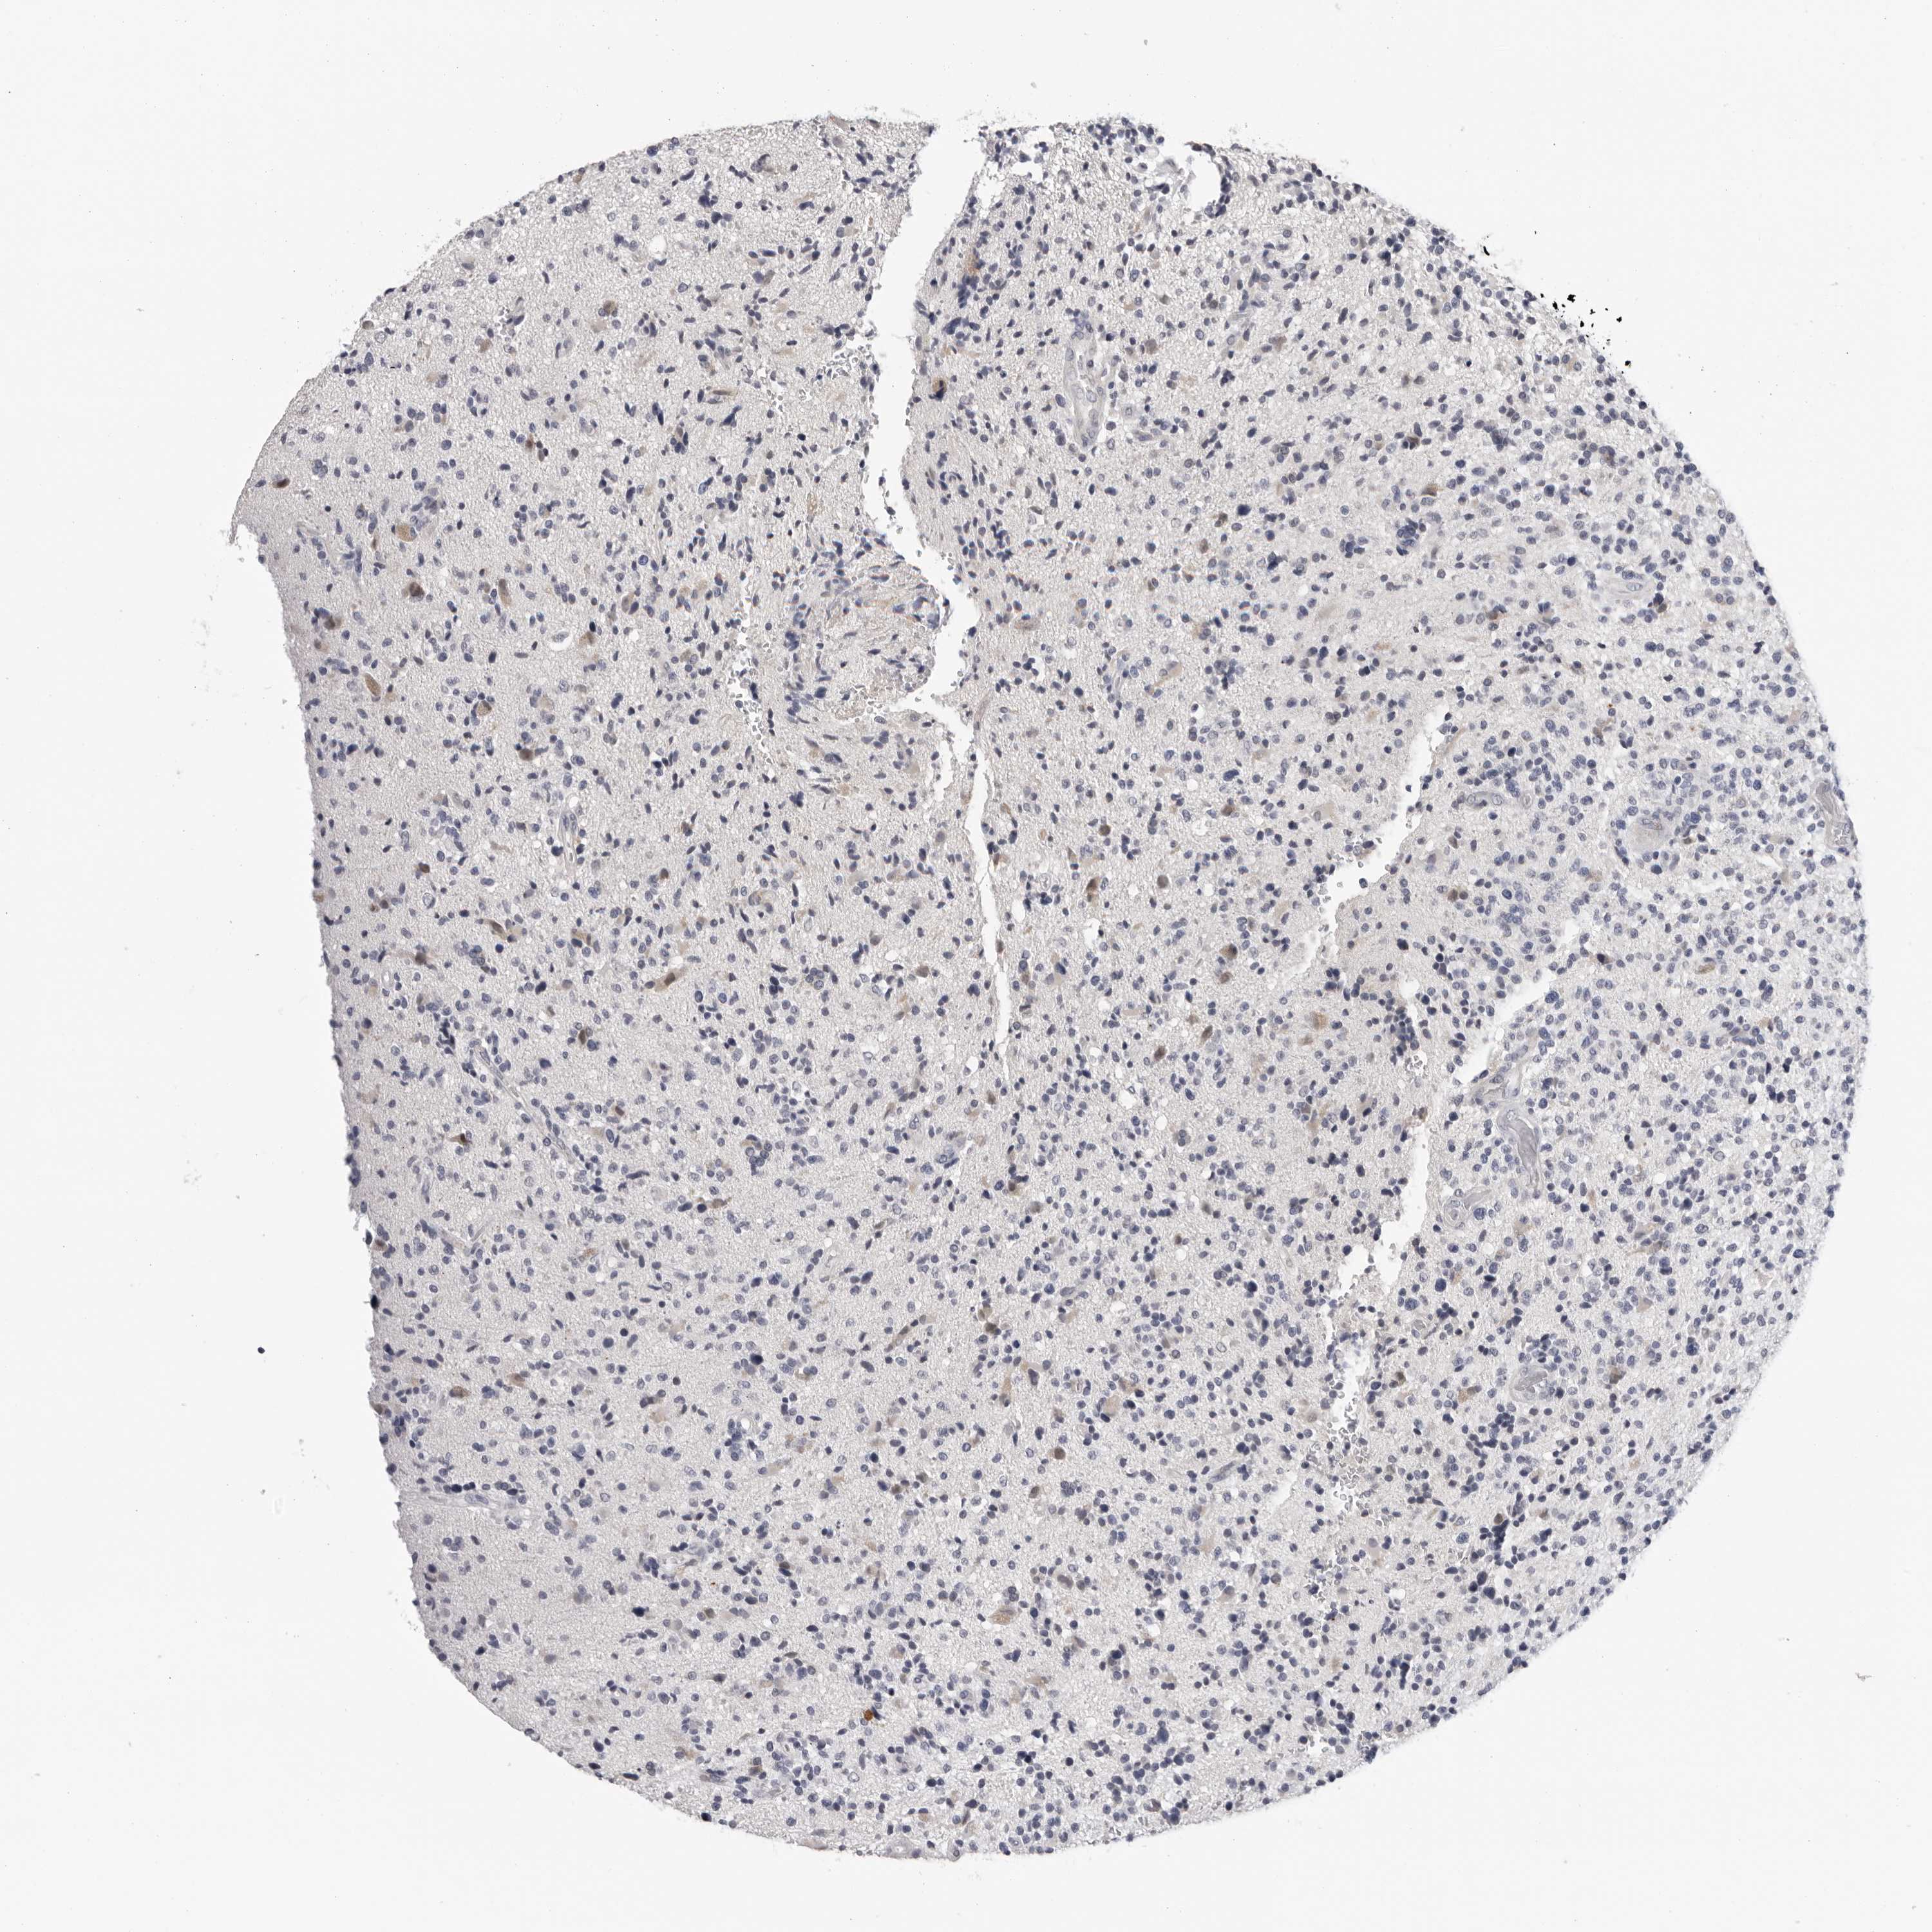

GLIOMA - Protein expressioni

A mouse-over function shows sample information and annotation data. Click on an image to view it in a full screen mode. Samples can be filtered based on level of antibody staining by selecting one or several of the following categories: high, medium, low and not detected. The assay and annotation is described here.

Note that samples used for immunohistochemistry by the Human Protein Atlas do not correspond to samples in the TCGA dataset.

Antibody stainingi

Antibody staining in the annotated cell types in the current human tissue is reported as not detected, low, medium, or high, based on conventional immunohistochemistry profiling in selected tissues. This score is based on the combination of the staining intensity and fraction of stained cells.

Each image is clickable and will lead to virtual microscopy that enables deeper exploration of all samples and also displays staining intensity scores, fraction scores and subcellular localization as well as patient and tissue information for each sample.

Antibody HPA024761

Antibody HPA029557

Glioma, malignant, Low grade

Glioma, malignant, High grade

Glioblastoma, NOS